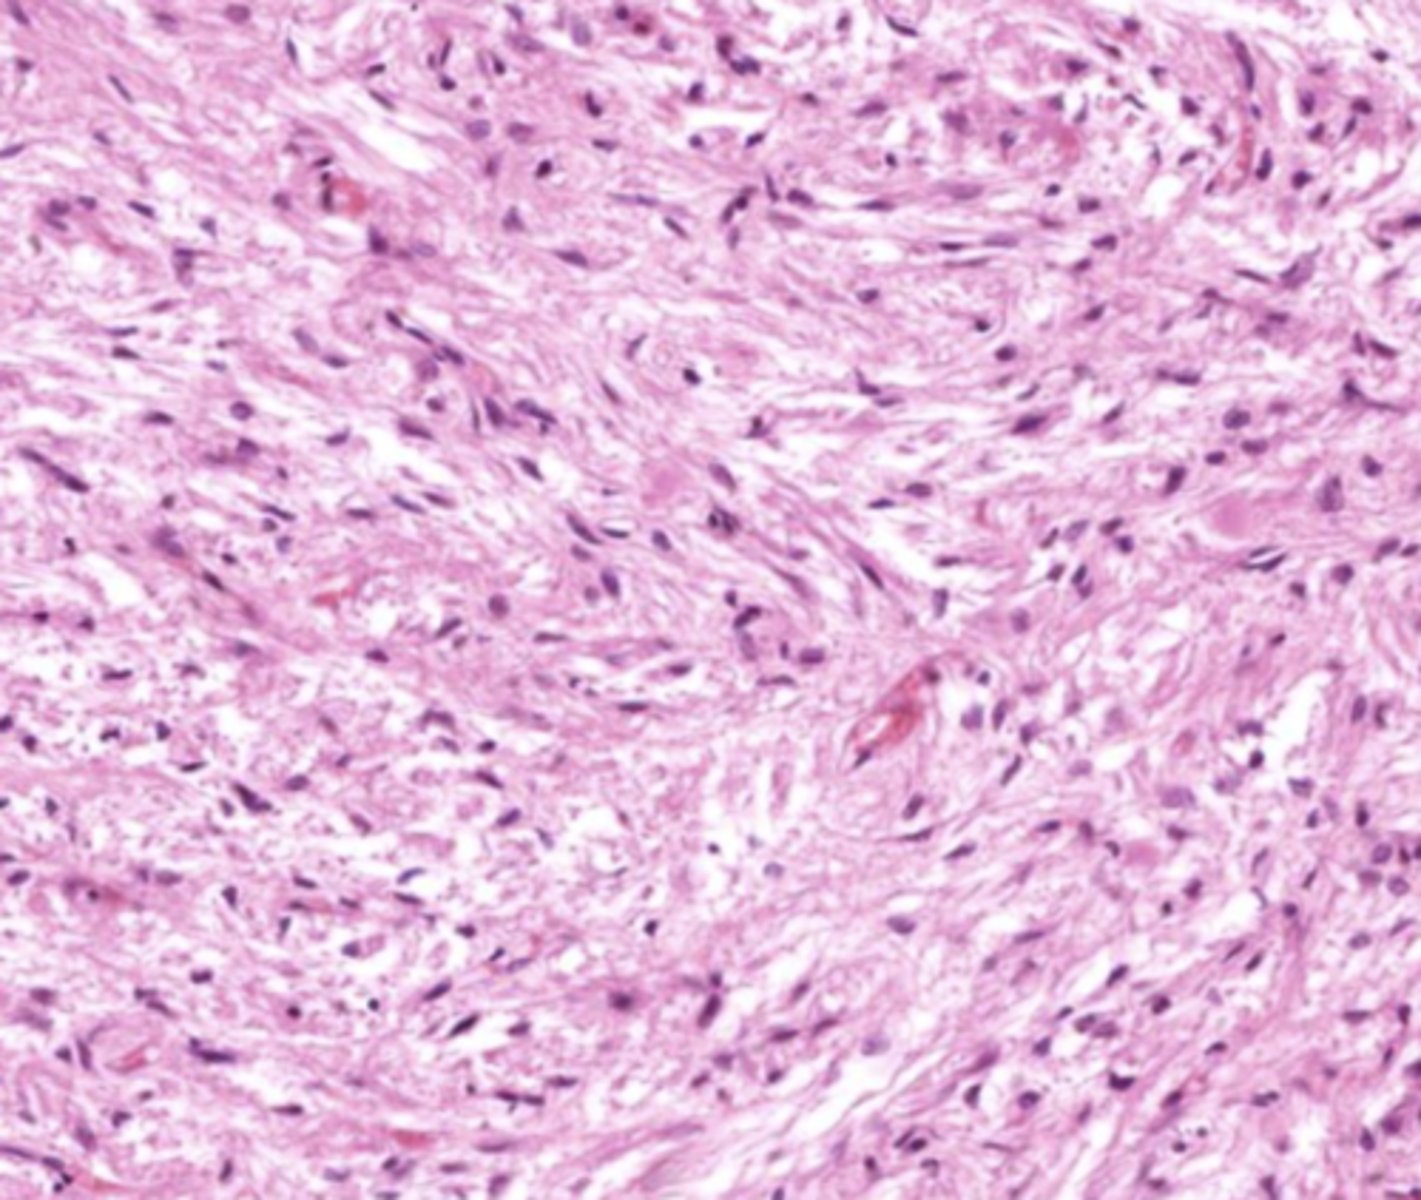

Dura mater

blue

Arachnoid mater

red

Pia mater

green

Epidural space

purple

Subdural space

between red and blue

Subarachnoid space

between red and green